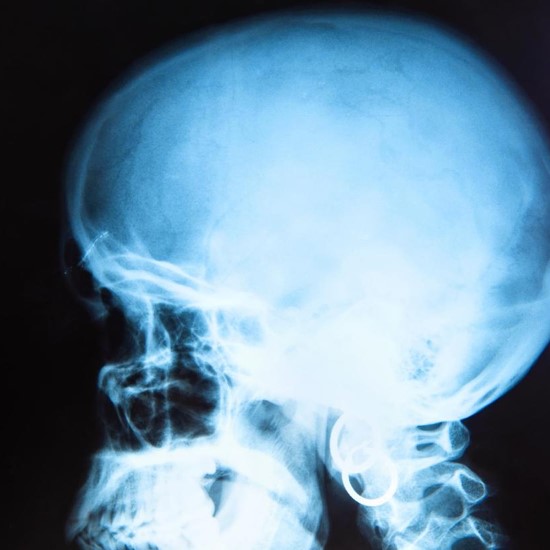

When a head injury results in a skull fracture, stem cells—the cells reserved to replace dead cells or repair damaged cells—rush to the site of the injury and start multiplying within 24 to 48 hours after the injury occurs. What hasn’t been fully known until now is how the cells know where and when to move, to multiply, and to make up for the lost cells. That is the subject of a new finding recently published in Science Signaling by Dr. Yingzi Yang, professor of Developmental Biology at Harvard School of Dental Medicine (HSDM).

Yang and her team of researchers specifically studied craniofacial bones to better understand stem cell activation, particularly stem cell migration and expansion, during tissue repair to identify signaling molecules that tell the stem cells where to go and how to expand.

“We looked at how these stem cells respond to injury, expand in number, migrate to the injury site, and differentiate into cells to regenerate lost tissue. Suture stem cells (SuSCs) are important for homeostasis and regeneration of cranial bone and can be used as a model to understand stem cell regulation for tissue regeneration at a distance,” said Yang.

The researchers found that after injury, the signaling molecules Cxcl12, Shh, and Ihh work together to help Gli1+ stem cells multiply in number. They also guide the stem cells and their descendants to migrate specifically to the damaged area and develop into bone-forming cells.

“Our findings represent a major step forward to allow us not only to harness the capacity of the SuSCs for cranial bone regeneration, but also to pinpoint the cell of origin that causes craniofacial defects such as craniosynostosis, a disorder resulting from premature suture closure, in genetic diseases and other conditions,” said Yang.

The finding highlights the vital role of suture stem cells, shedding light on genetic disorders that affect skull formation and conditions such as progressive osseous heteroplasia and fibrous dysplasia. By understanding the underlying mechanisms, better treatments could be found for these debilitating conditions.

“Currently, surgery is quite often the only option for treating these conditions. However, now that we know how natural healing is controlled, our hope is that it could open the door to non-surgical approaches,” said Yang.